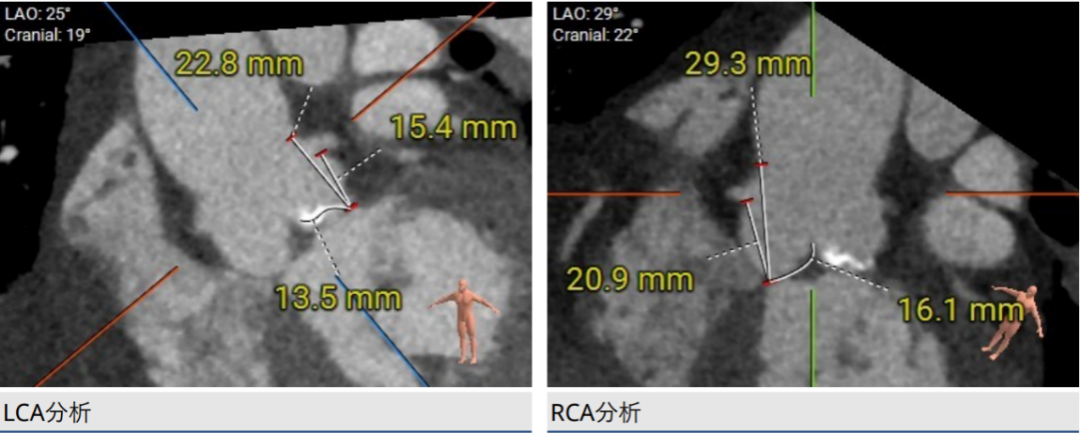

CT分析

主动脉根部结构

手术策略采用右侧股动脉为主入路,全麻配合食道超声进行。根据瓣环测量数据,初步确定选择Evolut PRO 29mm瓣膜。是否需要针对Type0型二叶瓣采用downsize策略,团队进行了详尽探讨,决定先行20mm球囊扩张,根据球囊形态和瓣周漏情况决定最终选型。